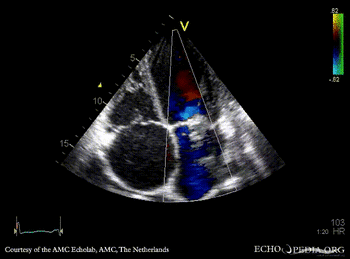

Severe prolaps of PMVL

PSAX: flattening of IAS, enlarged right ventricle PSAX: prolaps of PMVL